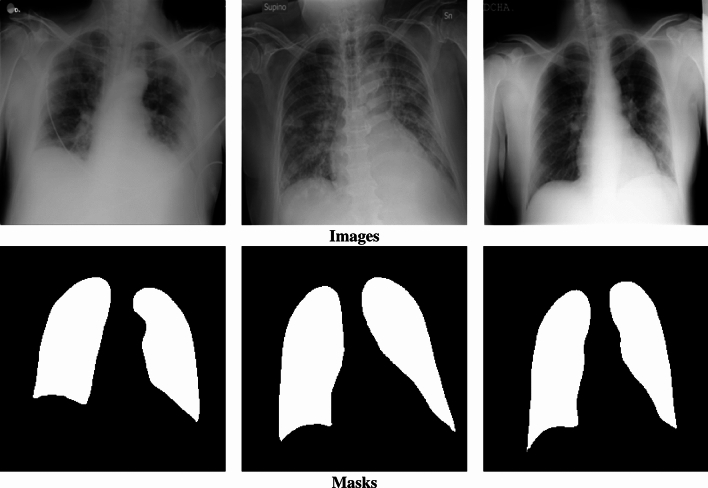

This research presents a novel ensemble fuzzy deep learning approach for brain Magnetic Resonance Imaging (MRI) analysis, aiming to improve the segmentation of brain tissues and abnormalities. The method integrates multiple components, including diverse deep learning architectures enhanced with volumetric fuzzy pooling, a model fusion strategy, and an attention mechanism to focus on the most relevant regions of the input data. The process begins by collecting medical data using sensors to acquire MRI images. These data are then used to train several deep learning models that are specifically designed to handle various aspects of brain MRI segmentation. To enhance the model's performance, an efficient ensemble learning method is employed to combine the predictions of multiple models, ensuring that the final decision accounts for different strengths of each individual model. A key feature of the approach is the construction of a knowledge base that stores data from training images and associates it with the most suitable model for each specific sample. During the inference phase, this knowledge base is consulted to quickly identify and select the best model for processing new test images, based on the similarity between the test data and previously encountered samples. The proposed method is rigorously tested on real-world brain MRI segmentation benchmarks, demonstrating superior performance in comparison to existing techniques. Our proposed method achieves an Intersection over Union (IoU) of 95% on the complete Brain MRI Segmentation dataset, demonstrating a 10% improvement over baseline solutions.